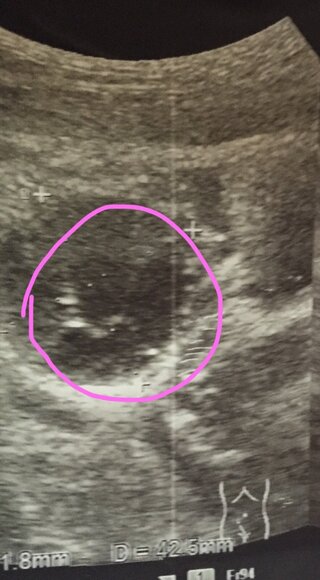

卵巣が腫れてるとのことでエコーを撮ってもらいましたがこの白いモヤモヤはなんです Yahoo 知恵袋

3 チョコレート嚢胞患者を高次医療機関へ紹介するタイミング サイズ エコー輝度 隆起性病変 日本産婦人科医会